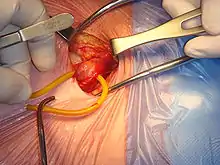

إصلاح الفتق يشير إلى العملية الجراحية لتصحيح الفتق (انتفاخ الأعضاء الداخلية أو الأنسجة من خلال وجود عيب في جدار تجويف الجسم). ويمكن أن يحدث الفتق في العديد من الأماكن، بما في ذلك البطن والأربية و الحجاب الحاجز والمخ وفي موضع عملية سابقة . وهناك أساليب عديدة مختلفة للإصلاح الجراحي لحالات الفتق، بما في ذلك رفو الفتق ورأب الفتق وبضع الفتق. وغالبًا ما يتم إجراء إصلاح الفتق كإجراء إسعافي.

ومن الصواب عموما إصلاح الفتق بسرعة من أجل منع حدوث مضاعفات مثل ضعف العضو المصاب، الغنغرينا، متلازمة تعدد خلل الأعضاء، والموت. ويمكن لمعظم الفتق البطني الإصلاح جراحيا، ونادرا ما يتطلب التعافى تغييرات طويلة الأجل في نمط الحياة. الفتق الغير مصاحبة لتعقيدات يمكن ان تصلح بالضغط واعادتها إلى مكانها وبعلاج ضعف العضلات أو الخلل الذي أدى إلى حدوث الفتق وتسمى العملية herniorrhaphy إذا حدثت مضاعفات، فإن الجراح يتحقق من صلاحية العضو المفتوق، ويستأصله إذا لزم الأمر.

التقنيات الحديثة لتقوية العضلات تشمل المواد الاصطناعية (الشبكة الصناعية) التي تجنب الإفراط في تمددالأنسجة الضعيفة أصلا (كما هو الحال في كبار السن، ولكن لا تزال هذة الاساليب مفيدة). يتم وضع الشبكة إما على الخلل (إصلاح الأمامي) أو أكثر من الأفضل أن يكون تحت الخلل (إصلاح الخلفي). وتستخدم في بعض الأحيان بعض الأدوات للحفاظ على الشبكة في مكانها. وتسمى هذه الطرق في كثير من الأحيان "الضغط الحر"، لانها على عكس الأساليب التقليدية القديمة، لا يتم سحب العضلات معا عن طريق الضغط.

على نحو متزايد، يتم تنفيذ بعض الإصلاحات من خلال جراحة المناظير.

ويشار أيضا جراحة بالمنظار على أنها ذات حد ادنى من التدخل، الأمر الذي يتطلب شق واحد أو أكثر للكاميرا وأدوات لإدراجها، في مقابل فتح "التقليدية" أو "المجهرية" لعملية جراحية، الأمر الذي يتطلب إجراء شق كبير بما يكفي ل تدرج يد الجراح في جسم المريض. مصطلح الجراحة المجهرية مضلل يشير إلى الأجهزة المكبرة التي استخدمت خلال عملية جراحية مفتوحة.